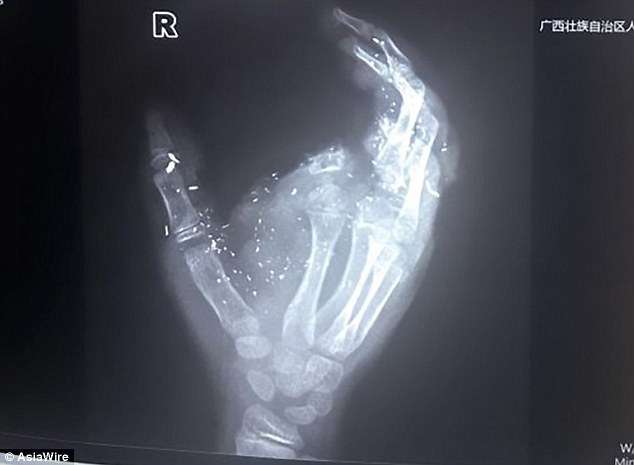

▼小明的右手食指被炸飛,其他手指受傷,眼睛也被炸傷了。他又痛又怕,直接暈了過去。家人連忙帶他去醫院治療,經過檢查,小明的眼球有異物、肺部挫傷、右手臂和手指有粉碎傷。醫生立刻為他做前臂皮瓣轉移修復術、拇指、中指、環指再植手術。

▼醫生介紹,小明被送到醫院時,斷離的食指沒有一起帶過來。他的斷指被炸得只剩一點點,手掌嚴重受損,幾根手指沒辦法供血,醫生考慮再三後決定不為他接食指,努力搶救其他手指。